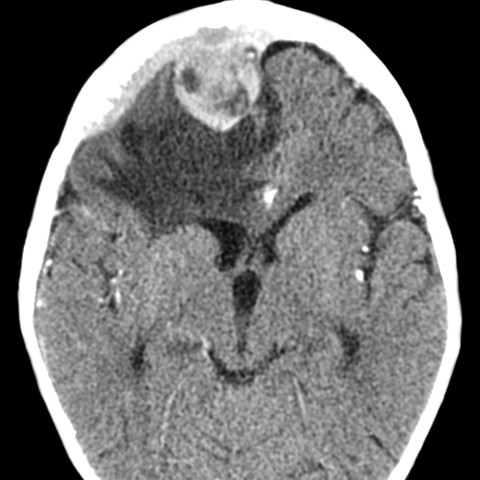

Neuroblastoma, metastasis